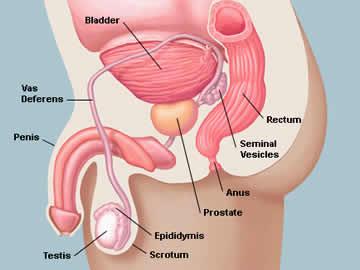

Enlarged Prostate /Prostate Cancer

Treating Prostate without SurgeryHomeopathic treatment of Enlarged Prostate Prostate_Cancer Most men, till they reach middle age or suffer from any problem related to the prostate ... Full story